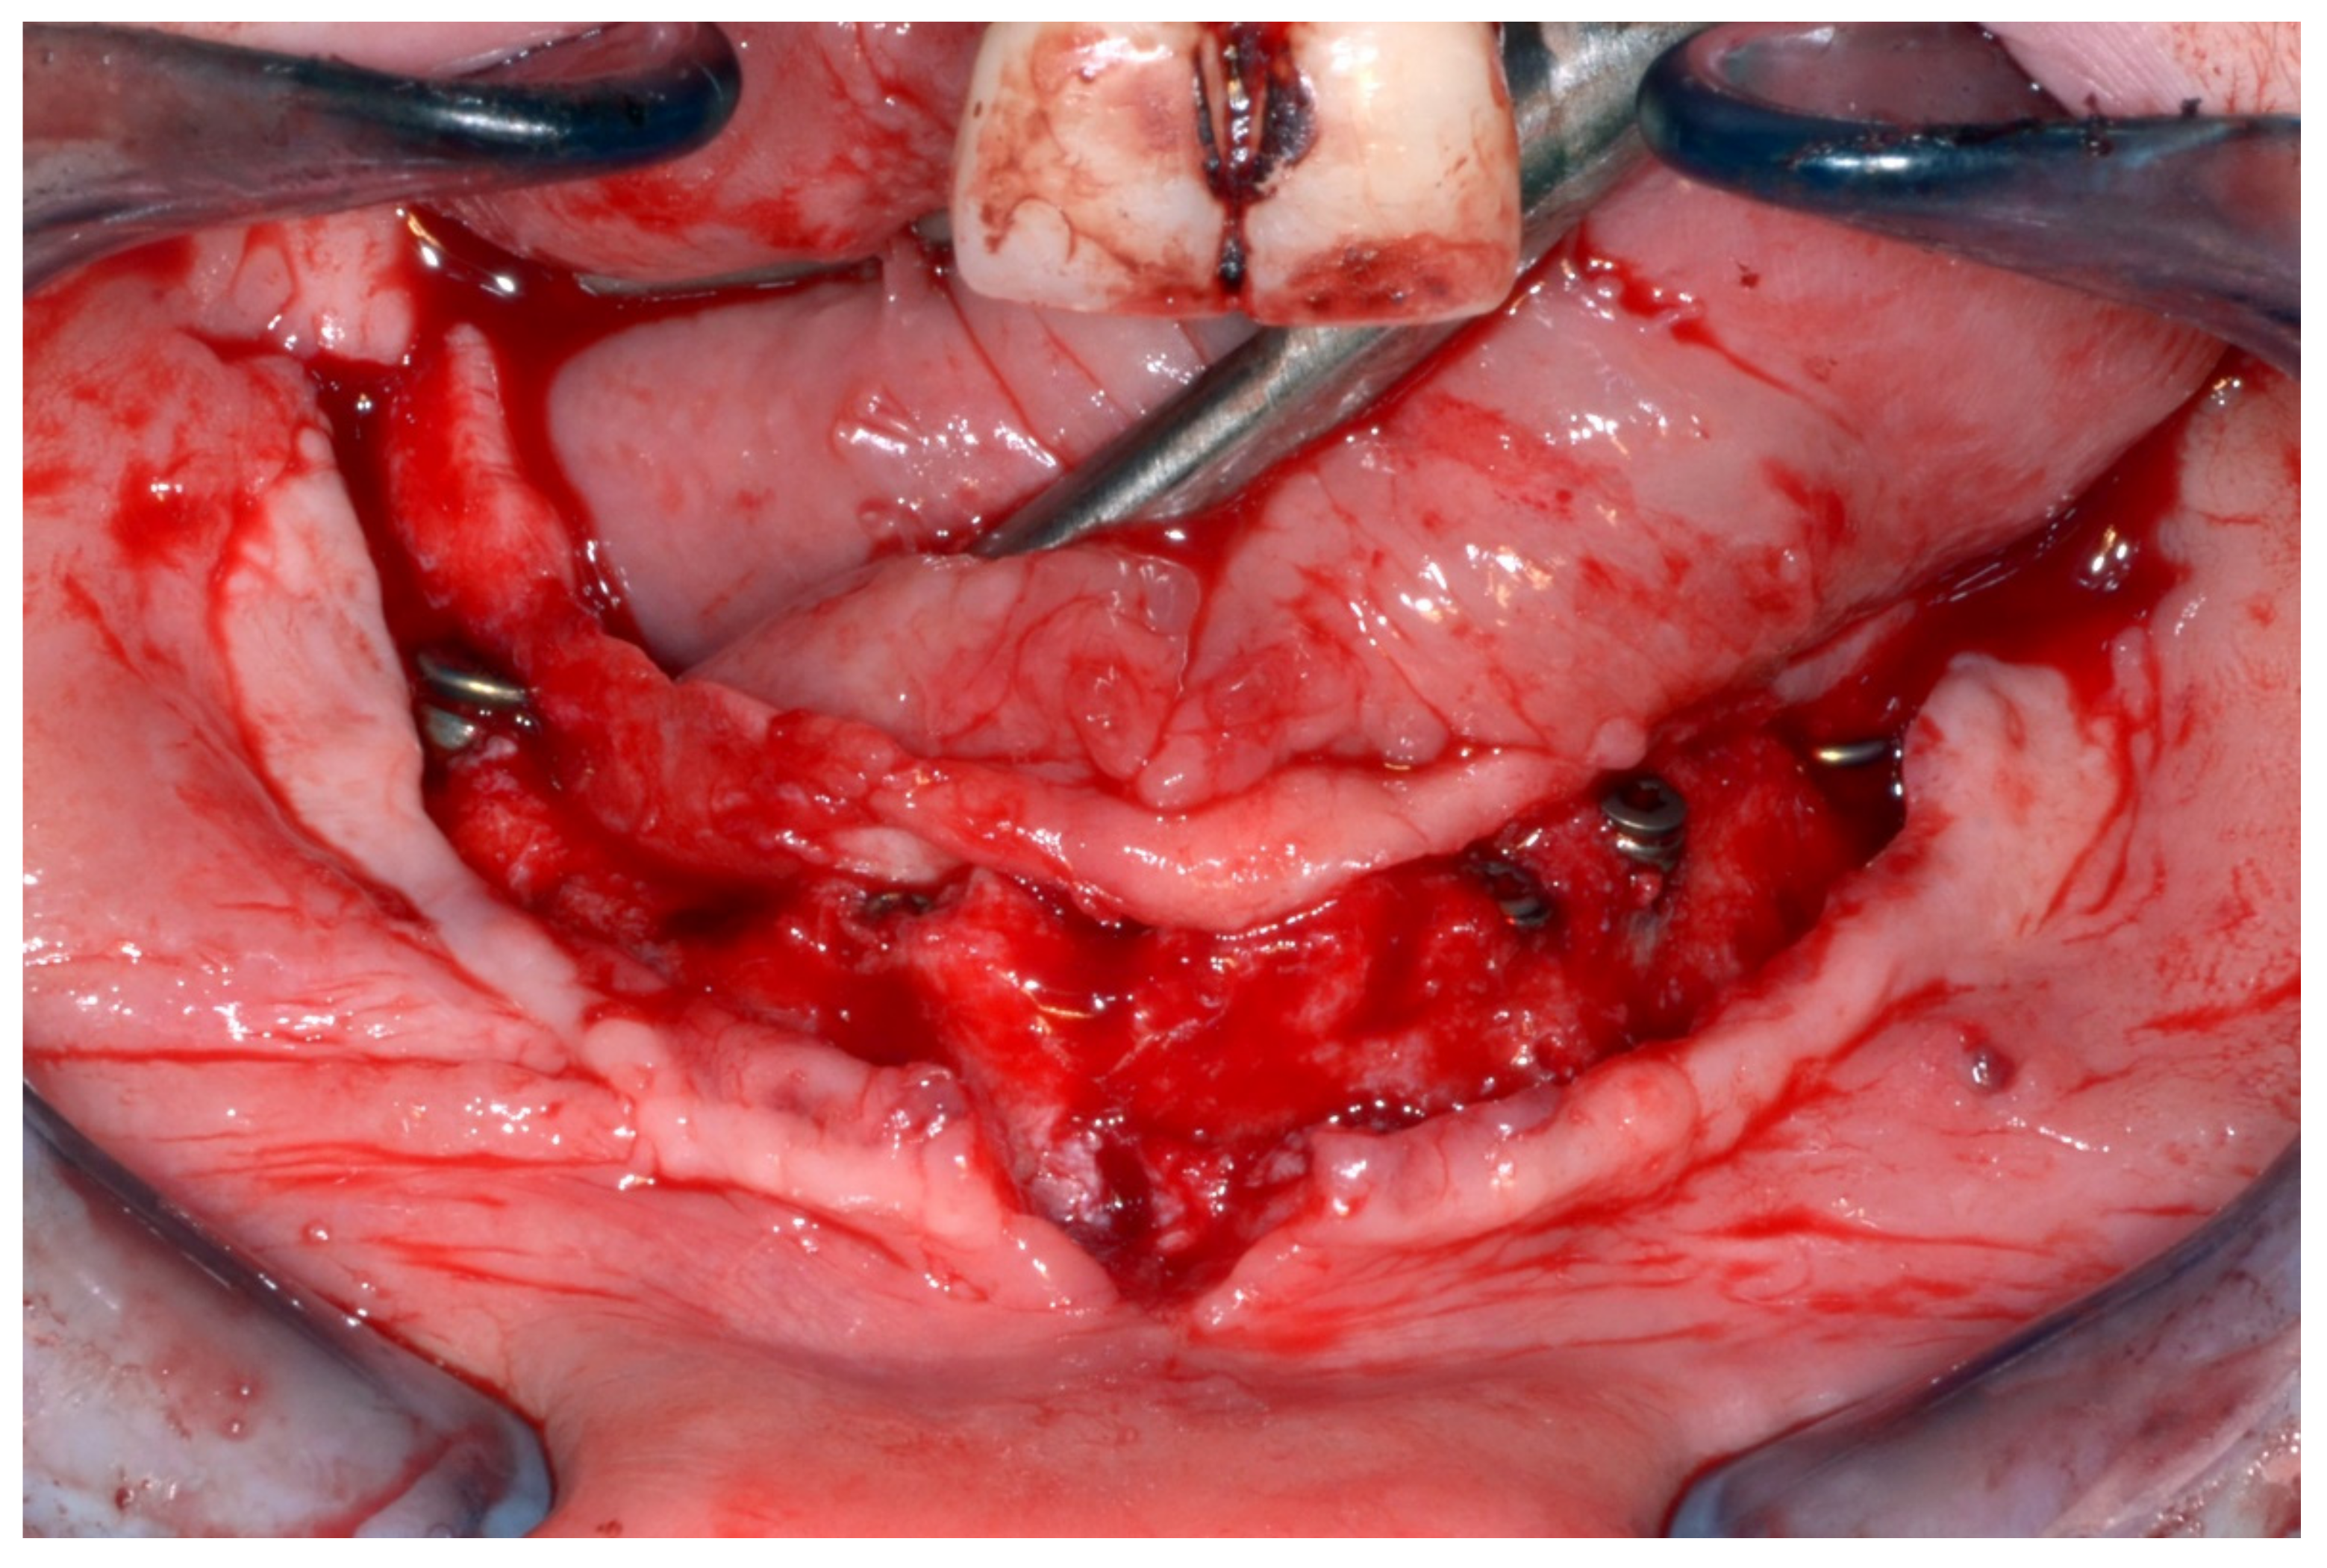

Figure 22.

Maxillary surgical drilling guides temporarily supported and fixed with mini-screws.

Figure 23.

Mandibular surgical drilling guides temporarily supported and fixed with mini-screws.